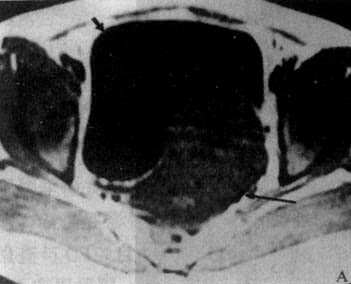

图4-5-6 女性骨盆正常MRI表现

T1WI矢状面,子宫肌层为中等信号强度(↓)子宫内膜为稍低信号强度(▽),膀胱内尿液为极低信号强度(↓)T2WI矢状面,子宫肌层信号降低(↓),子宫内膜信号增强(↓),膀胱内尿液信号明显增强(↓)